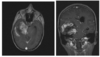

A Central American patient presents with new onset seizures. CT shows hydrocephalus, and muitiple calcified lesions. MRI

demonstrates rim-enhancing cysts throughout the brain. What is the most likely etiology?